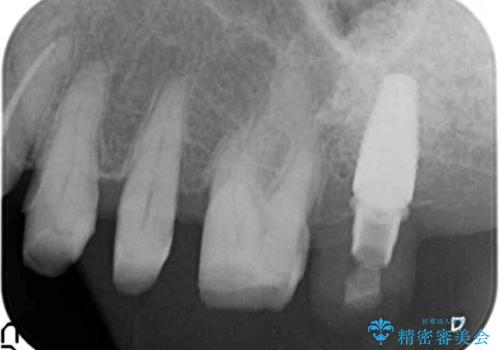

歯ぎしりに抵抗する歯周補綴 インプラント補綴

- 61万円(仮歯・フルジルコニアクラウン×4 ・インプラント・チタンカスタムアバットメント )費用は治療当時の料金となります

分岐部病変を併発していた歯は、抜歯としインプラントによる咬合機能の回復。残すことのできる歯は歯周治療後連結補綴を行い歯ぎしりに対抗します。

夜間のナイトガード装着は必須です。